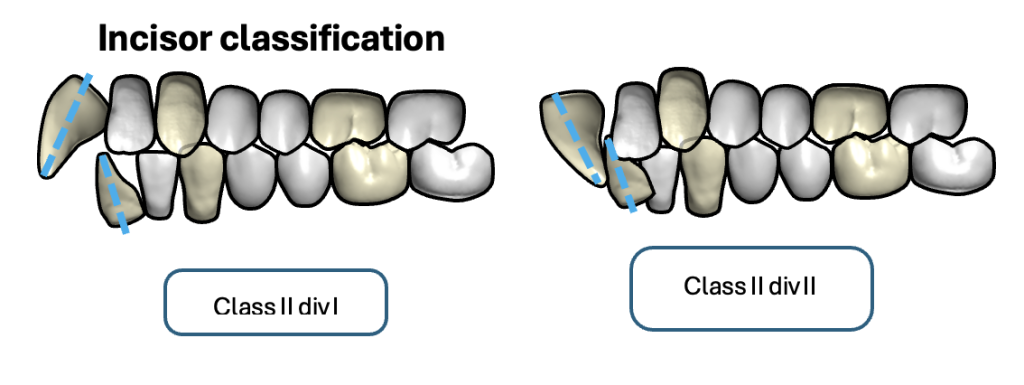

I can’t see much, but looks like class II, div 1. Your philtral column is absolutely convex as @chadisbeingmade describes it. It’s going to be lip-strain from that upper incisor protrusion I bet.View attachment 4176069this is the best photo I can take at the time, but i can see if i can get a better picture tomorrow

if I can get a CBCT I will send it. I'll try to avoid any extractions, but since that would be the cheapest option, my parents will probably opt for it.I can’t see much, but looks like class II, div 1. Your philtral column is absolutely convex as @chadisbeingmade describes it. It’s going to be lip-strain from that upper incisor protrusion I bet.

When the uppers sit forward and/or tipped out, the orbicularis oris has to contract to get a seal; that muscle pressure bulges the “central” upper lip so the philtrum reads convex. Your lower lip will catch behind the upper incisors usually (a lip-trap), deepening the labiomental fold too.

Not going to be bimax-tier unless jaw discrepancy is spotted which your ortho probably ruled out. In all honesty, they might go the safe route of premolar extractions which isn’t what you want. Perhaps TAD-anchored mechanics of sorts (?), they do these in aligners/braces I’m aware of, but not sure of what else, or if they’re even suitable for you / if your ortho is qualified to use them.